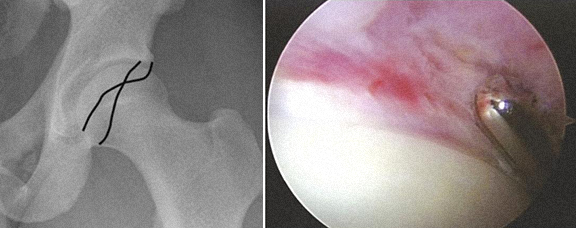

3 - Corpos livres visíveis nas imagens de Rx e TAC, e extração por artroscopia